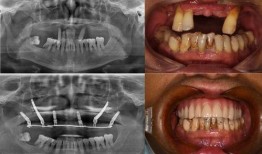

• 佛山种牙爆料事件最新,揭露行业乱象,患者权益如何保障?

最近佛山那边的种牙事件可是闹得沸沸扬扬的,咱们得好好来聊聊这个话题。你有没有想过,一颗牙齿的种植竟然能引发这么大的波澜?那就让我...